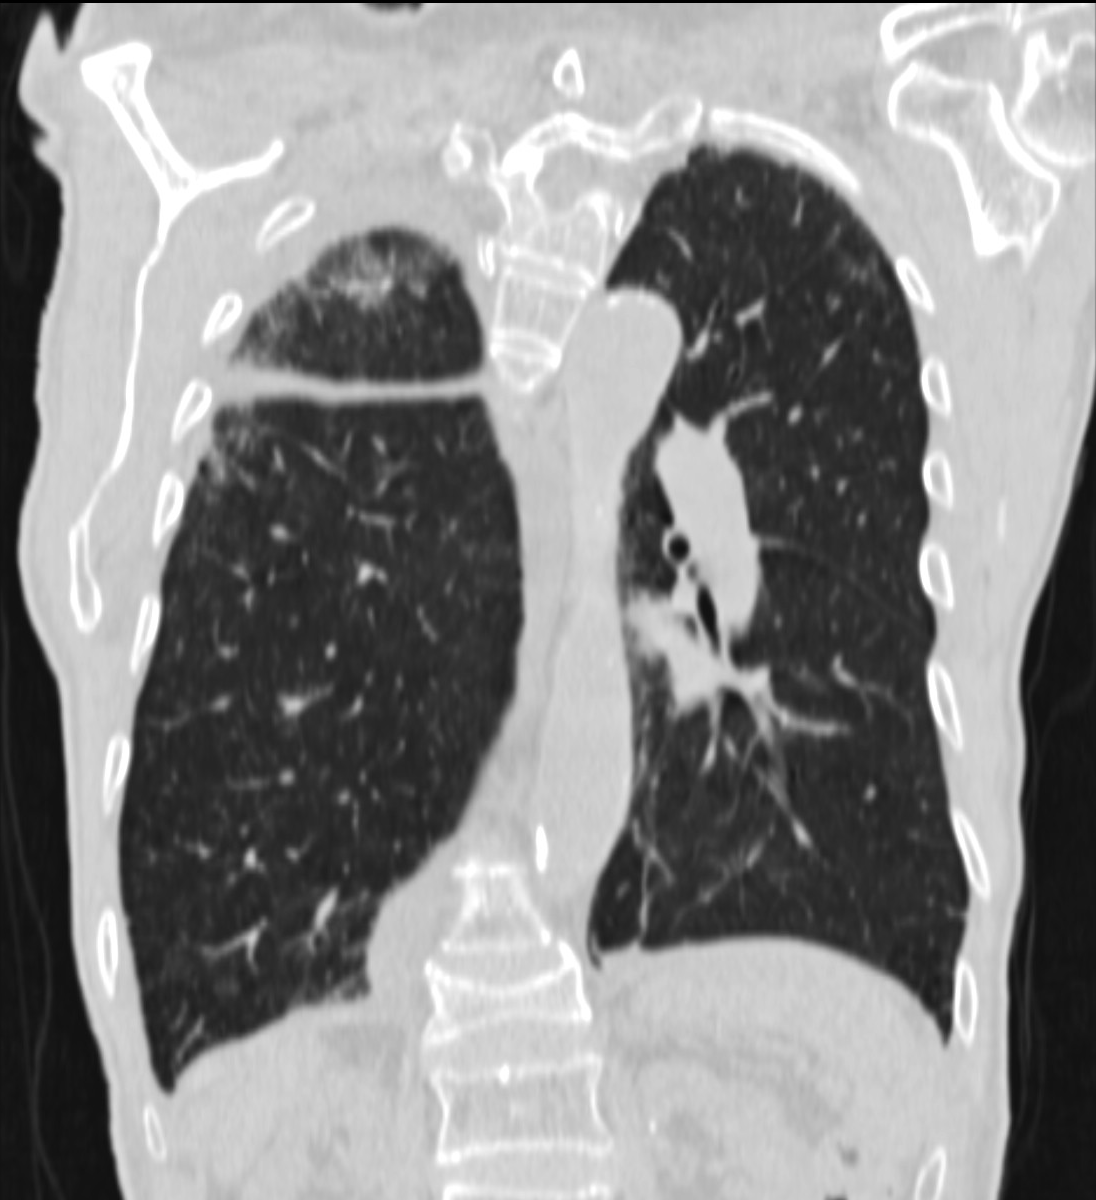

Unklare verdichtungen der lunge links. CAS Article PubMed Google Scholar. Die konventionelle Röntgenaufnahme der Lunge zeigte bipulmonale laterale Verschattungen verdächtig auf das Vorliegen einer atypischen Pneumonie Abb1. Neben der Lungenfunktionsprüfung werden zur Diagnose einer Lungenfibrose bildgebende Verfahren angewandt.

Dieser medizinische Begriff wurde für Sie übersetzt von. Verdacht auf Erkrankungen der Bronchien der Lunge der Pleura der Thoraxwand des Atemantriebs und der Atemmuskulatur. In addition to pneumology and pathology radiology is an essential discipline in the interdisciplinary diagnosis of interstitial lung diseases ILDs.

Verdacht auf Erkrankungen der Bronchien der Lunge der Pleura der Thoraxwand des Atemantriebs und der Atemmuskulatur. Neben der Lungenfunktionsprüfung werden zur Diagnose einer Lungenfibrose bildgebende Verfahren angewandt. Krankheiten die sich in den Alveolen dem terminalen Luftraum der Lunge abspielen haben ein anderes radiologisches Bild als solche die im Interstitium der Lunge lokalisiert sind. Verdichtung Röntgen Lunge. Die betroffenen Bereiche der Lunge sehen dann auf den CT-Bildern heller aus als das gesunde Lungengewebe. Wenn die hellen Stellen in der Lunge die Form eines Streifens haben dann sagt der Arzt dazu streifige Verdichtung. Es wird meist in der Neonatalperiode diagnostiziert und manifestiert sich klinisch in einer unterschiedlich ausgeprägten Tachypnoe. Die optimale Perfusions- und Ventilationsverteilung an dieser komplexen Oberflächenstruktur ist Voraussetzung für deren Diffusionseigenschaften Abb. Schranz Kinderherzzentrum der Universität Gießen danken.